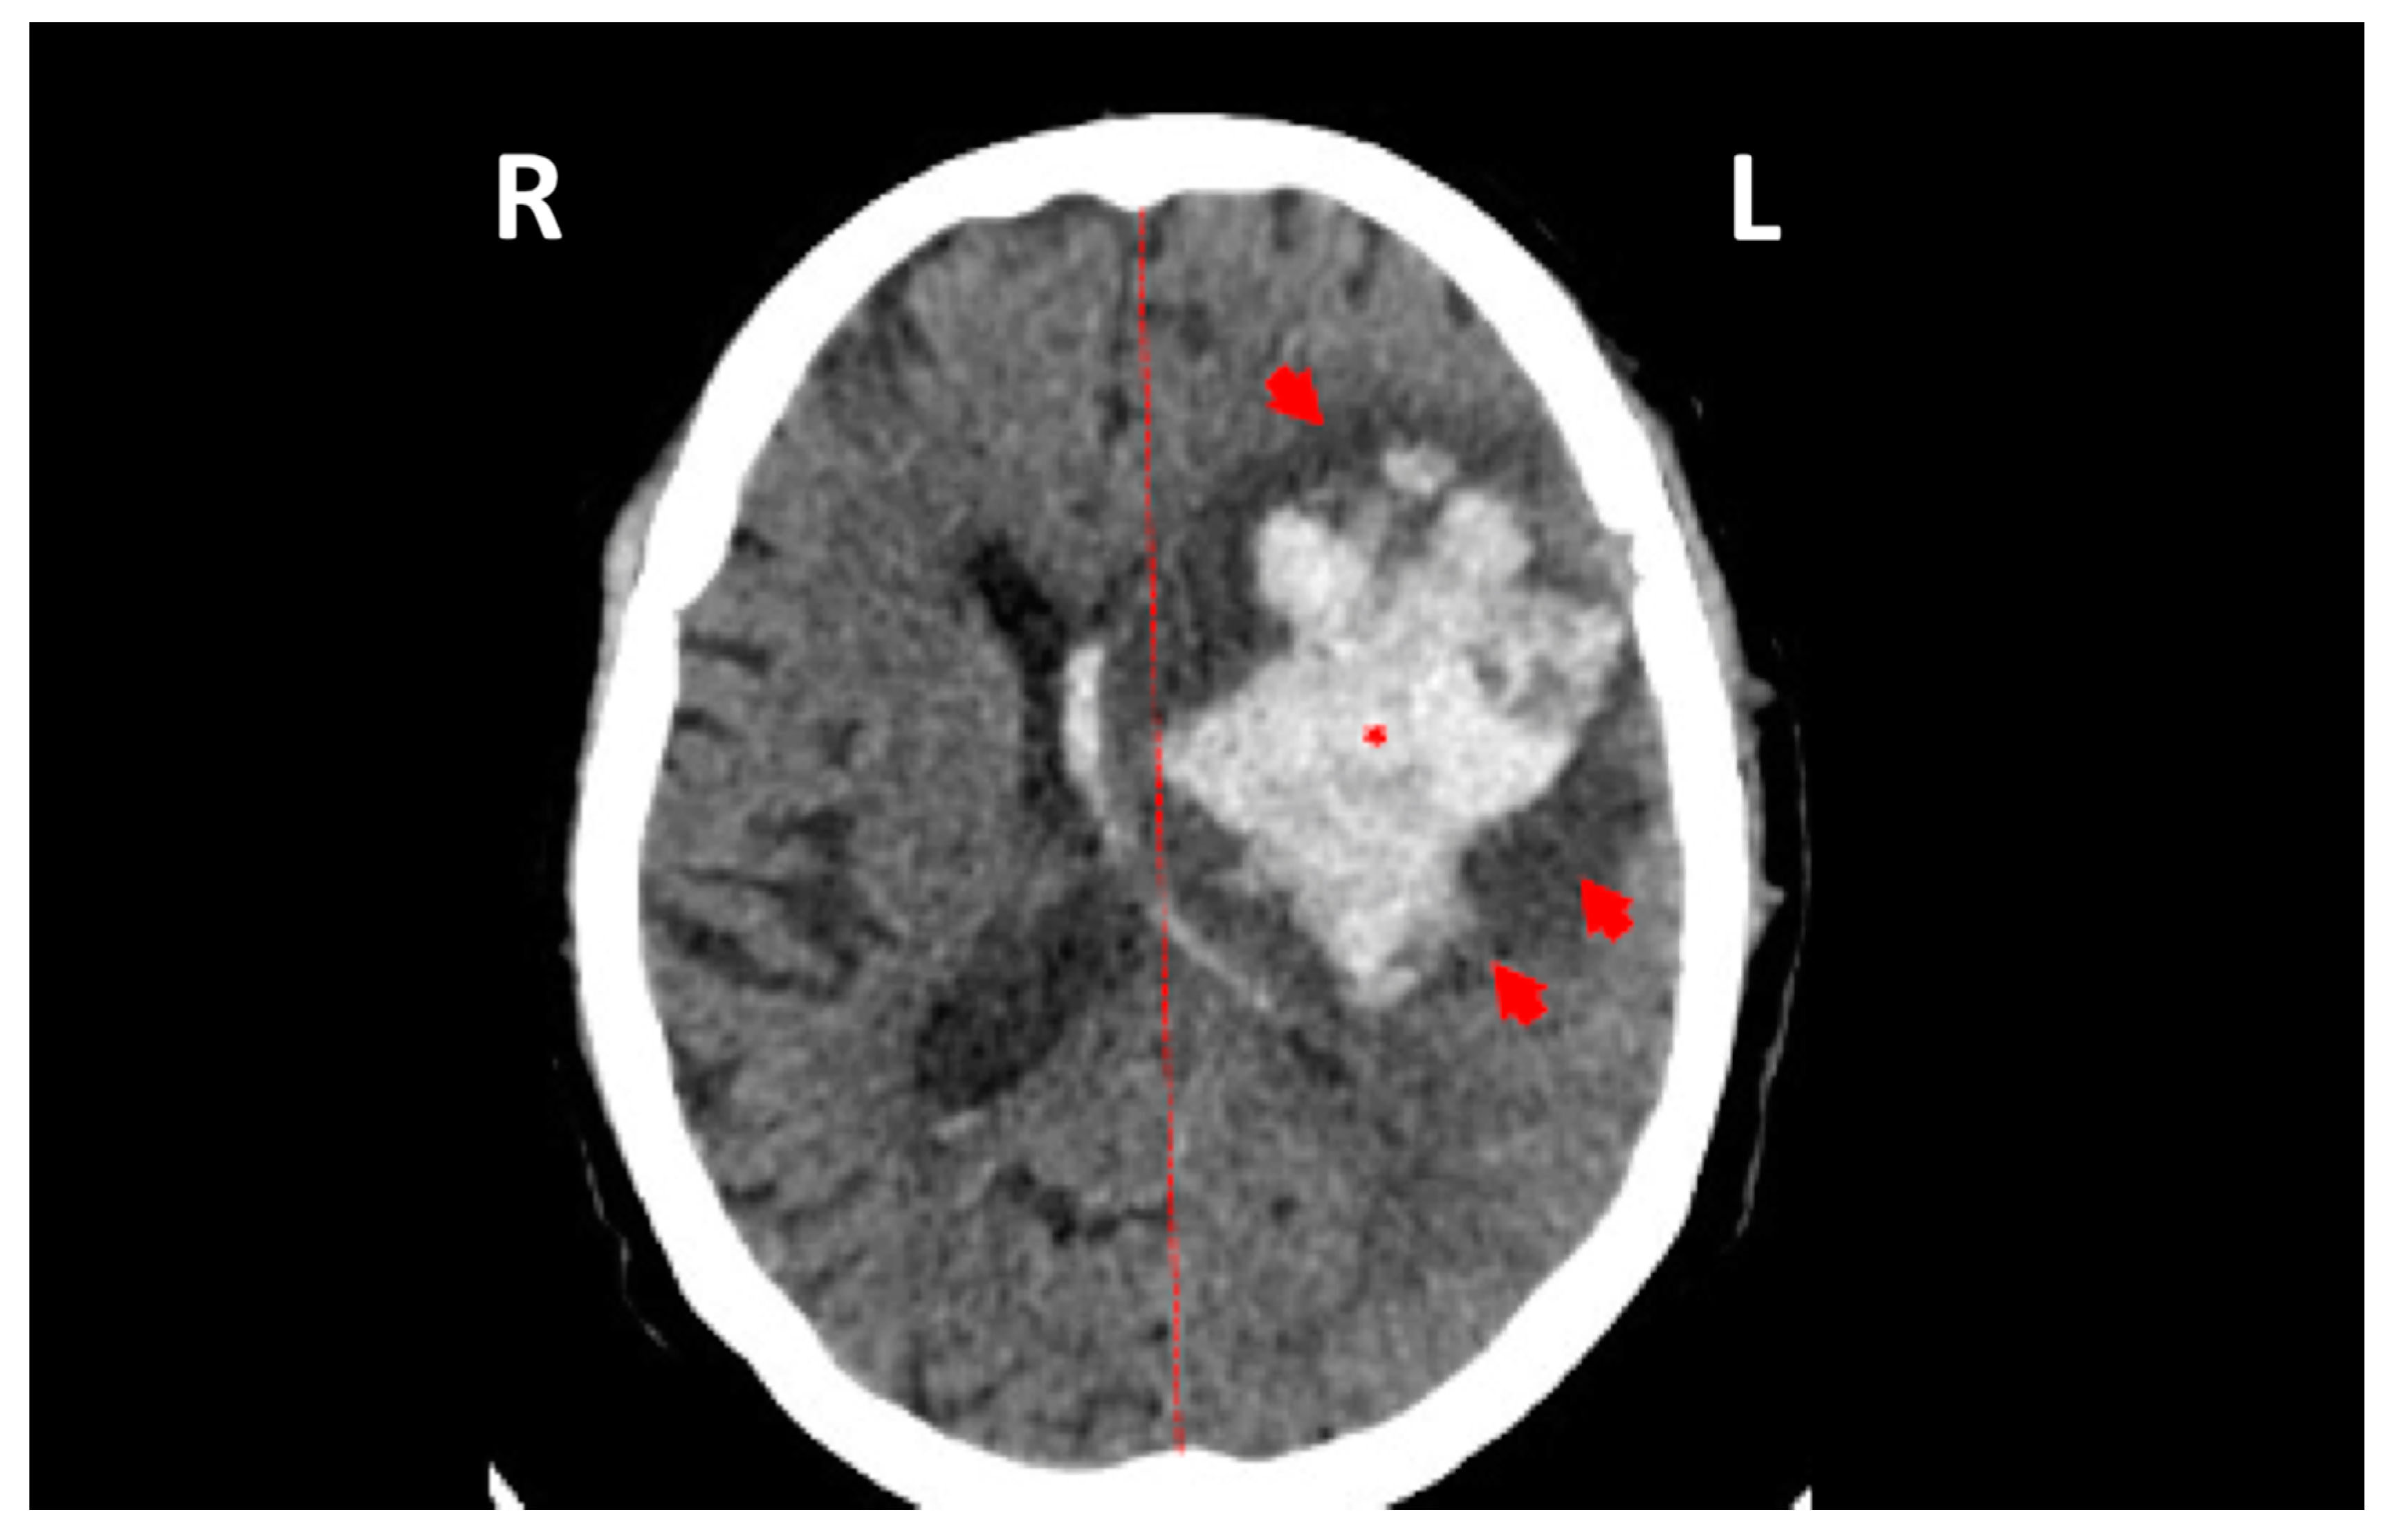

Milhim, B.H.G.A.; Estofolete, C.F.; Rocha, L.C.d.; Liso, E.; Brienze, V.M.S.; Vasilakis, N.; Terzian, A.C.B.; Nogueira, M.L. Fatal Outcome of Ilheus Virus in the Cerebrospinal Fluid of a Patient Diagnosed with Encephalitis. Viruses 2020, 12, 957. https://doi.org/10.3390/v12090957